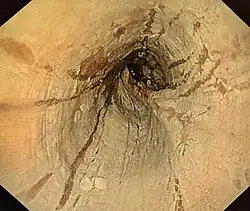

Die endoskopisch sichtbaren Veränderungen der Speiseröhre sind vielgestaltig und hängen von der Dauer der Krankheit ab. Neben dem sogenannten Baumring-Aspekt oder Baumring-Struktur und der hoch vulnerablen Krepp-Papier-Mukosa werden Längsfurchen, Ödem, weiße Exsudate und andere Veränderungen der Mukosa gesehen. Bei einem ausgeprägten Baumring-Aspekt spricht man von der „Trachealisierung“ der Speiseröhre, weil sie dann der Luftröhre (Trachea) ähnelt. Engstellen (Strikturen oder Stenosen) treten bei länger andauernder Krankheit auf. Da die erste Endoskopie oft im Rahmen einer Notfallsituation aufgrund der Bolusobstruktion erfolgt, werden die teils nur diskret ausgebildeten Veränderungen eventuell übersehen. Im endoskopischen Ultraschall sind gelegentlich Längsfurchen mit Verdickung der Mukosa darstellbar.

Zur Beschreibung des endoskopischen Befundes sollte die EREFS-Klassifikation (Akronym für Exsudate, Ringe, Ödem, Furchen und Strikturen) benutzt werden, die 2013 von Hirano et al. publiziert wurde. Eine vereinfachte EREFS-Version mit gleich guter Genauigkeit wurde 2019 vorgeschlagen[12].